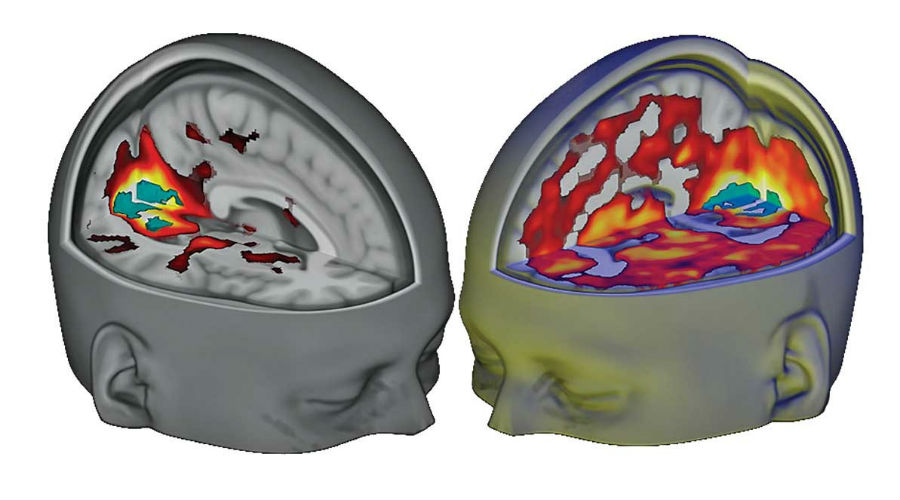

Onderzoekers hebben de effecten van de drug LSD op verschillende hersengebieden aangetoond.

Dat je van LSD roze olifantjes gaat zien, was al lang duidelijk. Maar nu weten we eindelijk hoe de psychedelische drug deze hallucinaties veroorzaakt. Want onderzoekers van het Imperial College London hebben de werking van LSD op verschillende hersengebieden in kaart gebracht met behulp van hersenscans.

De scans onthulden dat hersengebieden die normaal gesproken niet met visuele informatie omgaan, zich opeens gingen bemoeien met de visuele cortex – het hersengebied dat waarnemingen verwerkt. Dit zorgde ervoor dat de proefpersonen gingen hallucineren, terwijl ze hun ogen dicht hadden.

Een andere opvallende ontdekking is dat LSD ook de verbinding tussen neuronen vermindert in gebieden die verantwoordelijk zijn voor het zelfbeeld. Gevolg: mensen ervaren een out of body experience. Dit was al een bekend effect van de drug, maar nu weten de onderzoekers hoe dat komt.